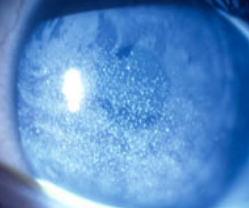

Corneal dystrophy

rare inherited disorder

sx: affect corneal transparency and can cause visual loss, it may cause pain if they cause corneal erosions.

Tx: corneal graft